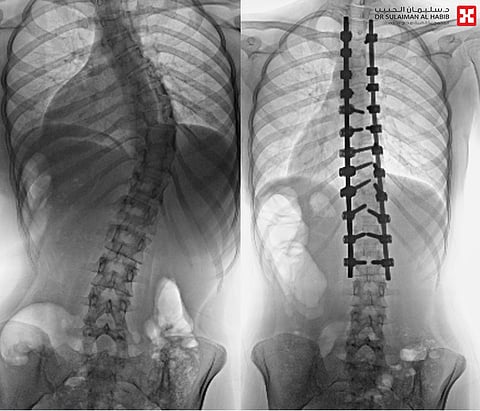

وقال د.صلاح الدين خليفة استشاري جراحة العمود الفقري بالمستشفى: إن معظم الحالات التي تمت معالجتها تراوحت درجة الانحراف فيها ما بين "45 إلى 85" درجة، وعانى معظمهم من أعراض كبروز الظهر وعدم تساوي الكتفين، والخصر وبروز أحد الوركين وجانب من القفص الصدري، وواجهوا أيضًا صعوبة في ممارسة الحياة الطبيعة؛ أما الأشخاص الذين عانوا من حالات انحراف حادة، فقد واجهوا مشاكل في التنفس، نتيجة تقليل انحناء العمود الفقري الشديد من مقدار المساحة داخل القفص الصدري، بدرجة جعلت من الصعب على الرئتين العمل بطريقة صحيحة.

واستطرد د.خليفة، أن النجاحات الطبية اللافتة التي حققها المستشفى في عمليات تقويم العمود الفقري، هي تأكيد على الإمكانيات الكبيرة التي يحظى بها المستشفى؛ كغرف العمليات الخاصة المجهزة، وأجهزة مراقبة الأعصاب، والإسناد النوعي المميز من تخصصات أخرى كالعناية المركزة والتخدير والعلاج الطبيعي ما بعد العملية.. ويتخلص المرضى من كل الأعراض؛ حتى الحالات الحادة التي كانت تعاني من ضيق النفس تعافت، وجميعهم غادروا المستشفى خلال أسبوع من العملية، وعادوا لممارسة حياتهم الطبيعية ببدن سليم، كما أن بعض المرضى الذين تأثروا نفسيًّا؛ خاصة أولئك الذين تغير مظهرهم الخارجي بسبب تبدلاتٍ كعدم تساوي الكتفين أو الوركين أو بروز الأضلاع، تخلصوا من أحمال نفسية ثقيلة كالخجل والاكتئاب وأقبلوا على الحياة براحة نفسية كبيرة، مدفوعين بزوال الأعراض وتحسن مظهرهم الخارجي.